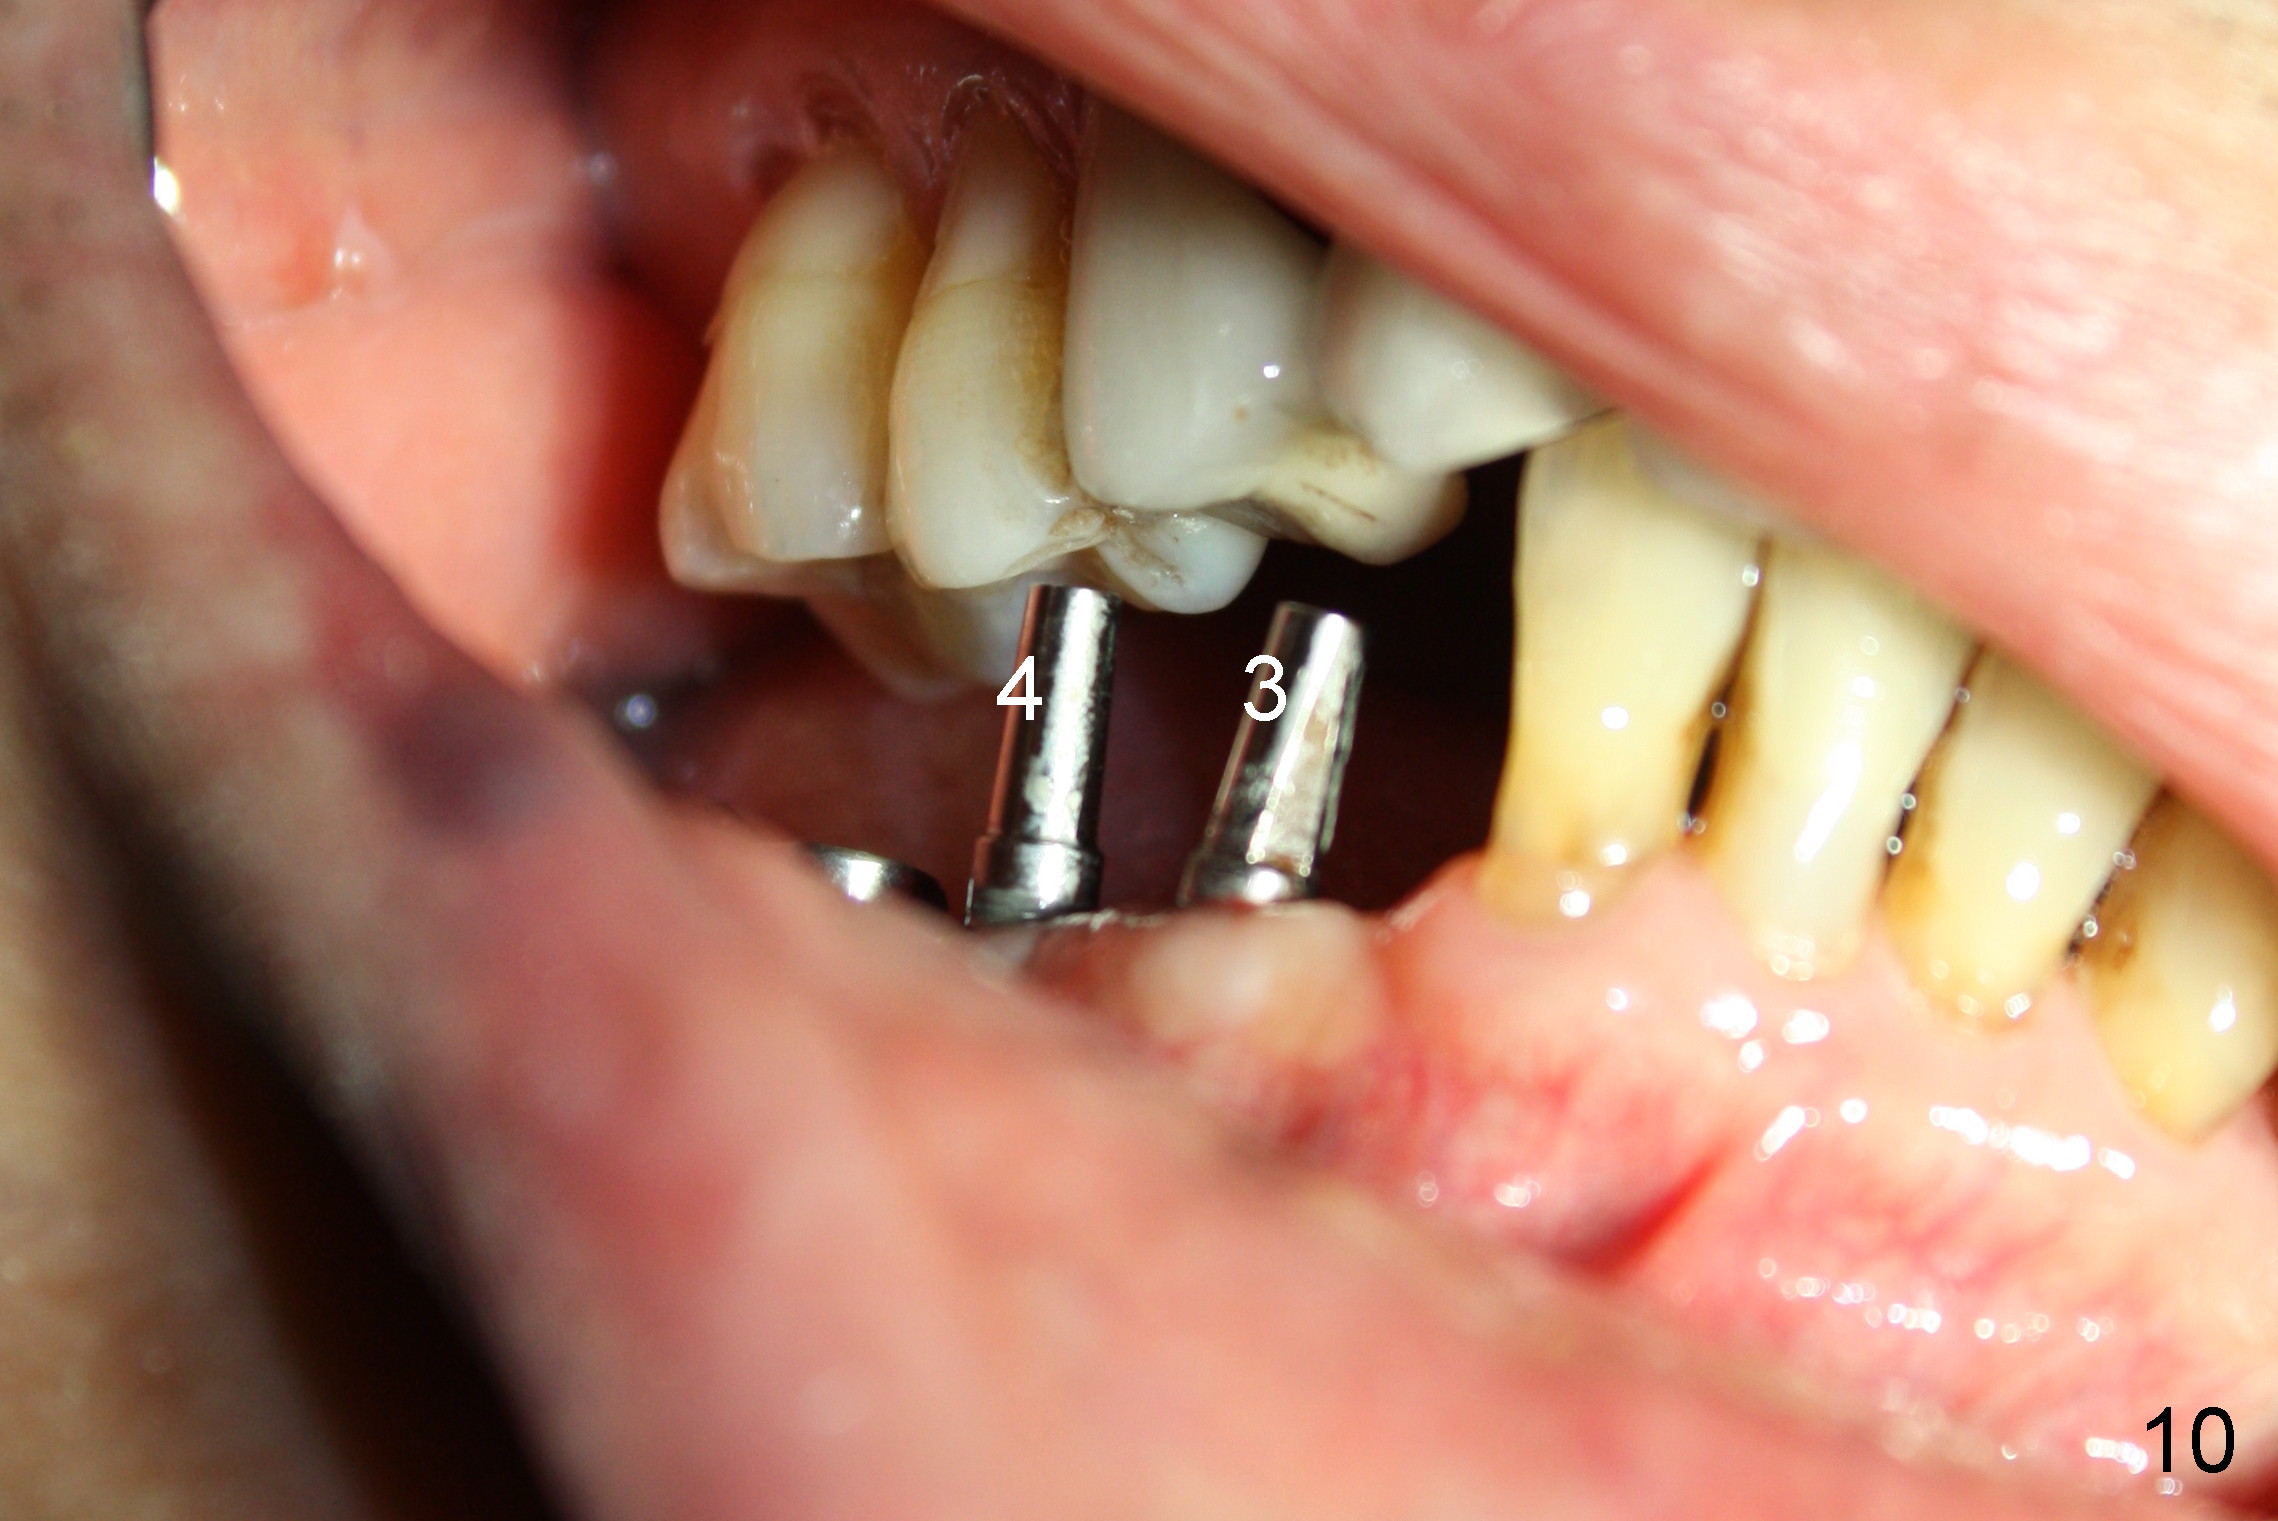

The lower right bridge (from canine (Fig.2: 3) to 1st molar (Fig.1: 6)) fails while a 77-year-old man is undergoing chemotherapy for urinary bladder cancer.  The abutments of the bridge are extracted without plan for implants (Fig.4).   Four months later, the patient returns for implants (Fig.3), but the ridge is narrow (Fig.5).  While 2 of 3x14 mm 1-piece implant are placed at the canine and 1st bicuspid sites, 2 piece ones at the 2nd bicuspid and 1st molar sites (Fig.6: 3.5x11 mm, 5x14 mm).  Soft (Fig.7-10) and hard (Fig.11) tissues heal 1 week (Fig.7) and 4 months (Fig.8-11).  There is minimal bone resorption 1 year 7 months post cementation (Fig.12,13, non-splinting).  It appears that narrow diameter implants are a valid solution to narrow ridge at the sites of the lower canine and premolar.  As long as there are enough implants for function, the crowns are not necessary to be splinted.  Surprisingly, the patient starts flossing after implant restoration.  Retrospectively an immediate provisional bridge should have been fabricated.